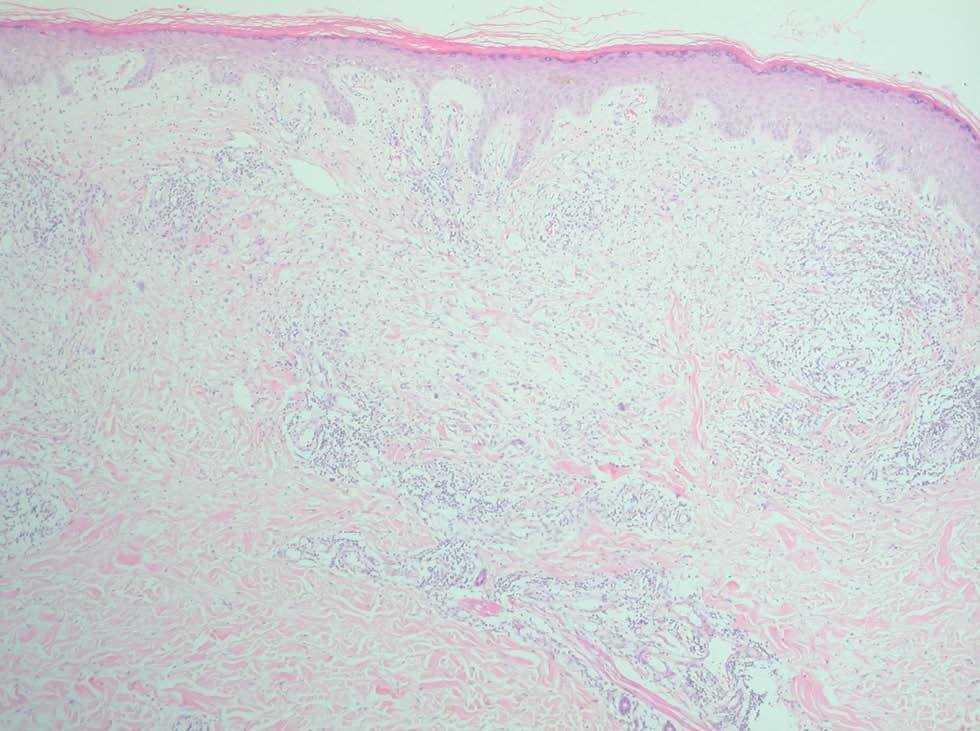

Una mujer de 52 años sin antecedentes de interés, salvo haber padecido 5 años antes una anemia ferropénica por metrorragias en tratamiento con hierro vía oral, consultó por la presencia de lesiones, asintomáticas, de unos 4 meses de evolución, localizadas en las extremidades. La paciente refería que habían aparecido en primavera y que había sufrido dos episodios previos de lesiones idénticas, 3 y 4 años antes, ambos iniciados en época estival y de unos 3 meses de duración. Las lesiones habían desaparecido espontáneamente en la primera ocasión y tras una pauta corta de esteroides por vía oral en la segunda, sin que se llegase a un diagnóstico. En la exploración física se objetivó la presencia de pápulas y placas eritematosas, de pequeño tamaño (5-15 mm), sensibles al tacto, de superficie lisa, confluentes en algunas zonas, situadas en las piernas, los antebrazos y el dorso de las manos, localización esta última donde las lesiones adoptaban una morfología anular (figs. 1 y 2). El resto de la superficie cutánea, palmas y plantas estaban indemnes. Con la sospecha clínica de granuloma anular se realizó una biopsia escisional de una de las lesiones. En el estudio histopatológico la epidermis estaba conservada y en los dos tercios superiores de la dermis se apreciaba un infiltrado linfohistiocitario con células gigantes que se distribuía en empalizada rodeando zonas de necrobiosis, no observándose fenómenos de elastorrexis ni de elastofagocitosis (fig. 3). Las pruebas complementarias realizadas, que incluyeron una bioquímica básica, hemoglobina glucosilada, hemograma, velocidad de sedimentación globular, proteinograma, inmunoglobulinas, complemento, factor reumatoide, anticuerpos antinucleares, marcadores tumorales, pruebas de función tiroidea, radiografía de tórax, ecografía abdominal y serología de lúes, virus hepatotropos y virus de inmunodeficiencia humana, no pusieron de manifiesto ningún hallazgo patológico. Con el diagnóstico de GA diseminado y en función del carácter autorresolutivo de los dos primeros brotes decidimos adoptar una actitud expectante. Aproximadamente a los dos meses el cuadro entró en regresión y a los 6 la paciente se hallaba libre de lesiones y así permanece un año después.

Fig. 3.--En los dos tercios superiores de la dermis se aprecia un infiltrado linfohistiocitario con células gigantes en empalizada rodeando zonas de colágeno degenerado (hematoxilina-eosina × 100).